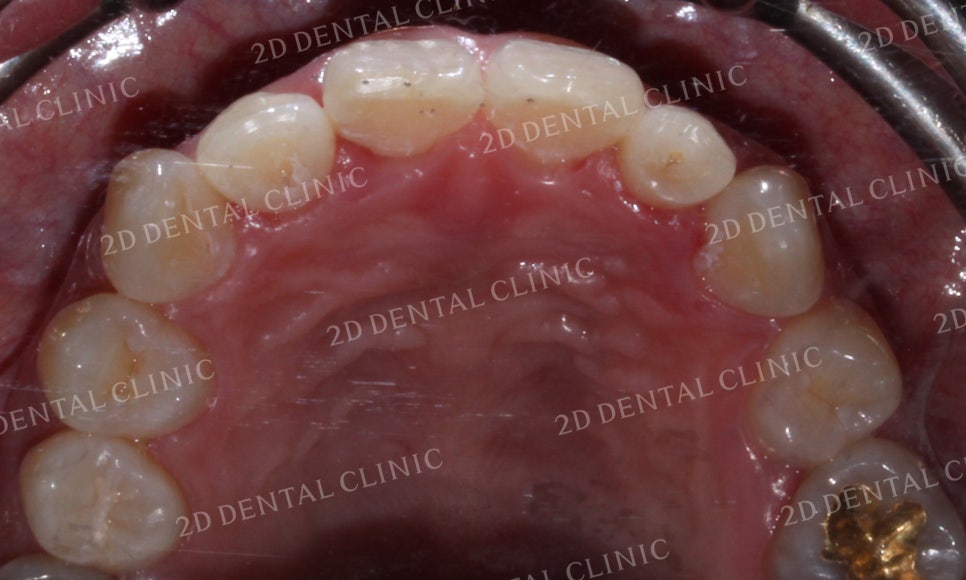

상악의 설측면 사진입니다.

교정 전 중절치의 나비치아 증상이

크게 완화된 모습이 가장 눈에 띄는데요,

견치의 후방에 있던 공간도 구치부 치아의 이동으로

많이 채워진 모습입니다.

비교적 작은 사이즈였던 좌측 측절치는

치아의 재배열로 어느 정도 보완된 모습이네요!